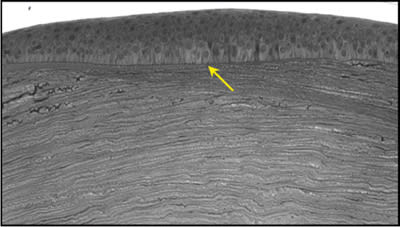

Our work has clearly shown that at least initially, keratoconus is a corneal disease with an anterior corneal focus. However, eventually the entire cornea becomes involved. Although the literature describes cracks, breaks, and ruptures of the anterior limiting lamina (ALL) (Leibowitz and Waring, 1998; Rabinowitz, 2005), our research has revealed a far more extensive involvement of the ALL in the pathophysiology of keratoconus. Centrally in the cone, more than 50 percent of the ALL is affected, and over expansive areas it is completely lost (Figure 2) (Horne et al, 2007).

Currently, we are also researching lamellar organization and are close to explaining how ectasia occurs. We know that the disease process causes a loss of ALL and the anterior interweaving stromal lamellae, all of which contribute to corneal thinning. However, even with these losses, we have reported a surprising increase in the overall number of lamellae found in the keratoconic cornea (Mathew et al, 2009). The reason for this increase is that the lamellae have broken down into smaller units. This discovery of the unraveling of stromal lamellae could be the key missing factor that explains ectasia in keratoconus and post-refractive surgery, which cannot be explained by simple thinning alone. This lamellar fragmentation possibly leads to a general weakening of the corneal infrastructure, provoking ectasia. CLS